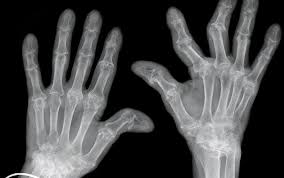

16+ Article About Rheumatoid Arthritis PNG. Spriggs, m.d., mph, facp — written by the healthline editorial. Learn all about rheumatoid arthritis, from symptoms, diagnosis, and treatments, to its types, diet tips, and how it differs from osteoarthritis.

Points to remember about rheumatoid arthritis. Rheumatoid arthritis is a type of chronic (ongoing) arthritis that occurs in joints on both sides of the body, such as hands, wrists and knees. The major goals for a patient with ra are

Basic information about rheumatoid arthritis, including common symptoms and treatment.

Find our complete video library. Rheumatoid arthritis (ra) is the most common type of autoimmune arthritis. Although there's no cure for rheumatoid arthritis, early treatment and support (including medicine, lifestyle changes. Treatments depend on the severity and stage of your ra symptoms and signs.